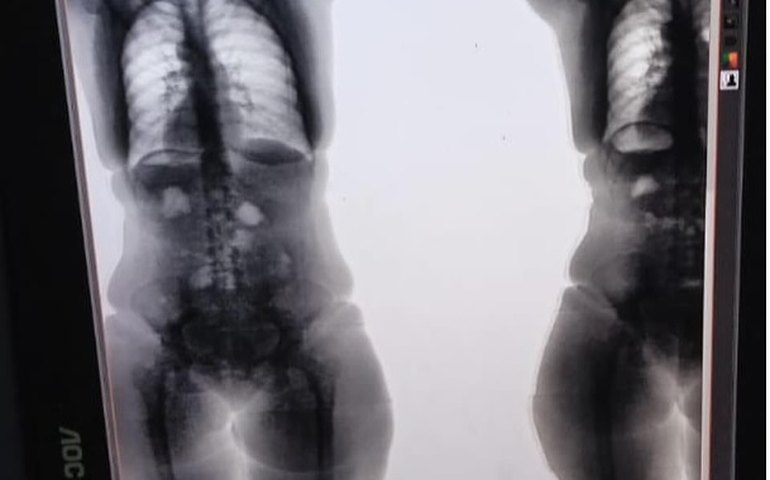

Os ilícitos foram encontrados devido o uso do escaneamento corporal

A Polícia Penal flagrou e impediu que cinco mulheres entrassem com drogas dentro do sistema prisional nesse fim de semana. Um desses casos I.S.P. de 26 anos, estava com entorpecente dentro do corpo, material detectado com o auxílio do bodyscan, que faz varredura corporal interna.

A policial penal responsável pela revista explicou como encontrou o ilícito nas mulheres. "Assim que observamos algo estranho nas imagens do bodyscan, iniciamos os procedimentos para confirmar a presença do que seria um ilícito. Para reiterar a nossa suspeita, decidimos repetir o exame. Após um tempo esperado, foi solicitado à visitante que passasse pelo equipamento novamente. Dessa forma, ficou confirmado que o corpo estranho continuava no mesmo local, sem alteração. A própria visitante fez a extração do material, e ao nos entregar o produto, confirmou que era maconha ", afirmou a policial penal Adriana Gil.